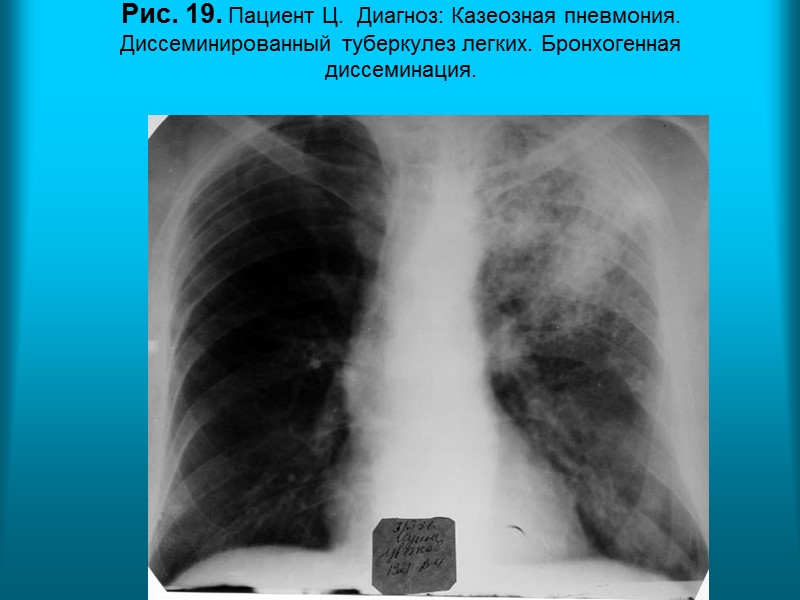

Н.С. Воротынцева. С.С. Гольев Рентгенопульмонология Рис. 19. Пациент Ц. Диагноз: Казеозная пневмония. Диссеминированный туберкулез легких. Бронхогенная диссеминация.